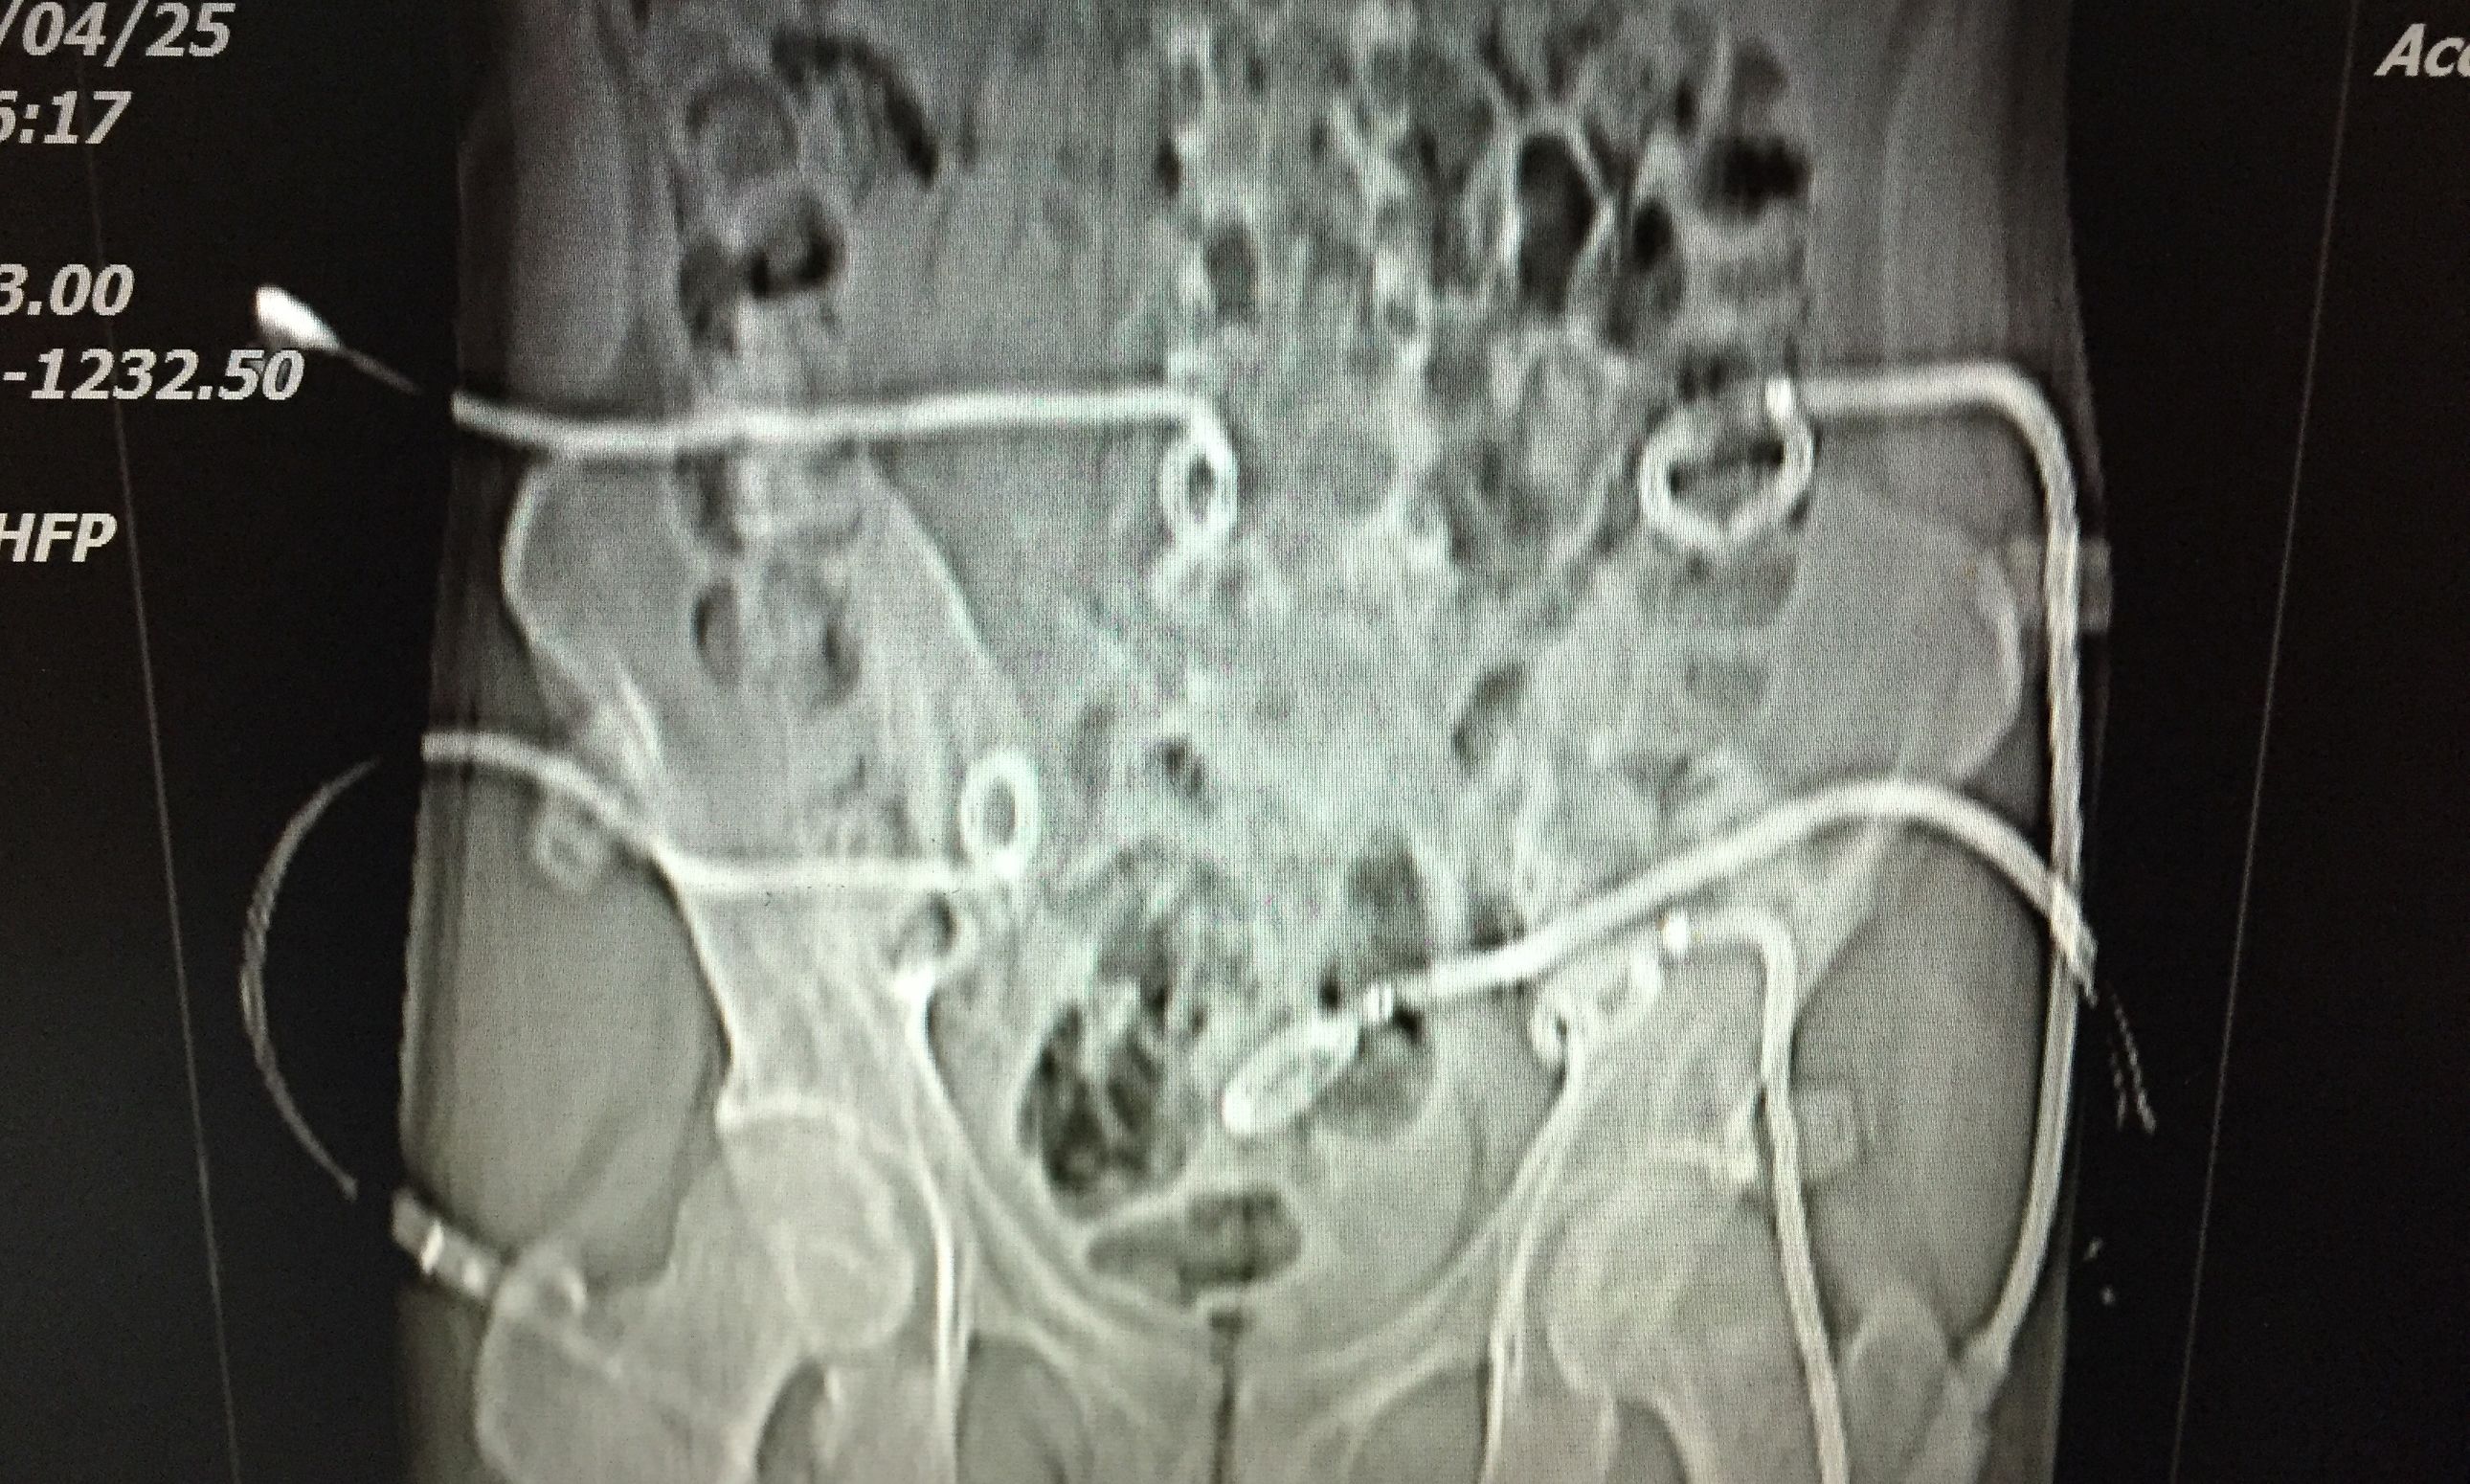

我们对患者在门诊进行充份置管引流(白色条状物5根)

在患者持续引流状态下,并联合抗痨治疗。如下图所示,脓肿完全吸收。患者痊愈。